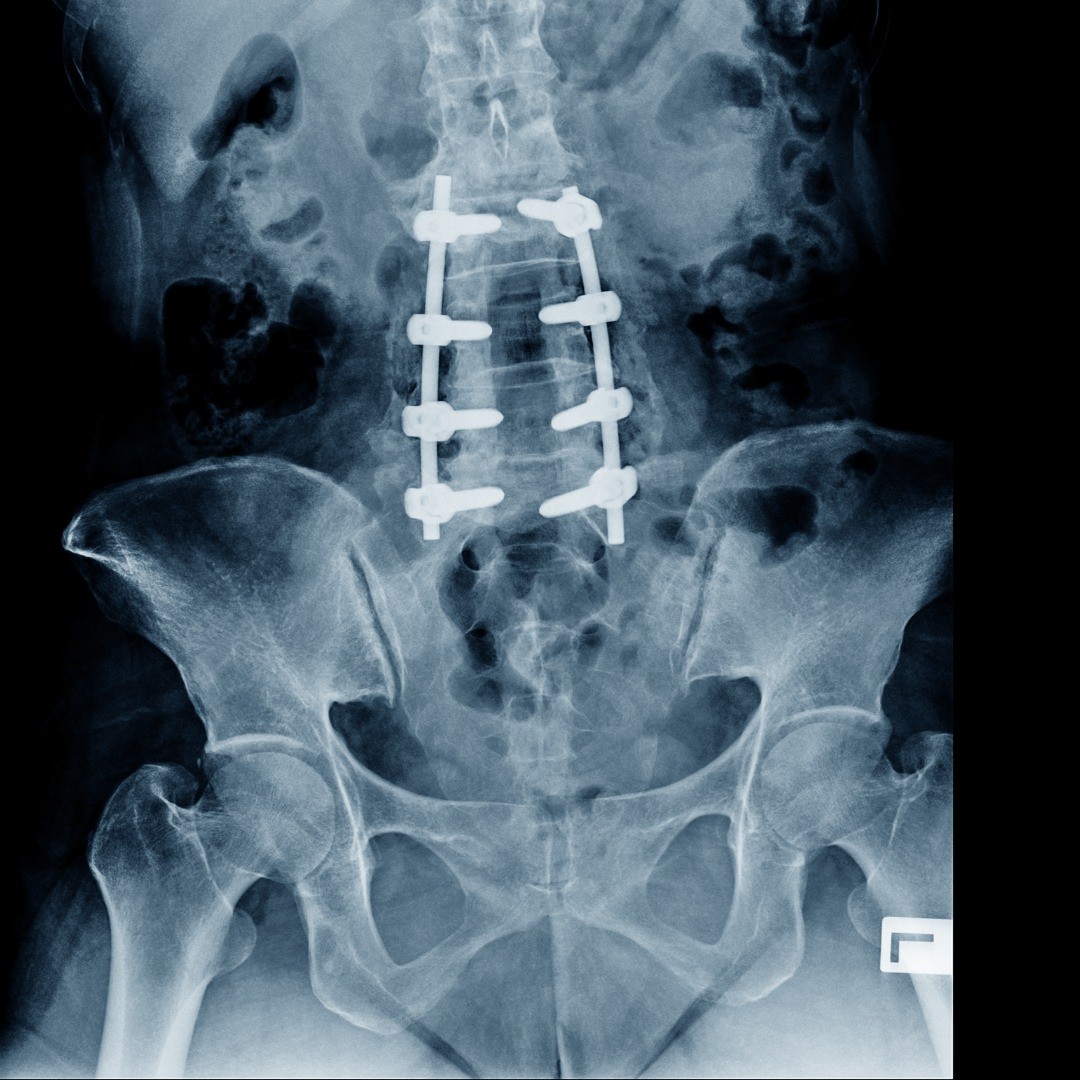

If other treatment options for your spine condition have been exhausted, we will take your medical history and perform a physical examination based on your symptoms to see if you are a good candidate for a laminectomy. Medical images, such as x-ray, magnetic resonance imaging (MRI) or computed tomography (CT scan) of your spine will show if vertebral displacement is present.

During a laminectomy, the patient is under anesthesia. An expert board-certified neurosurgeon makes a small incision over the affected vertebra and carefully retracts the muscles to reveal the spine. The spinous process, the bony protrusion from the back of the spine, is removed and then the lamina of the impinging vertebrae. If there are any bony growths of the foramina (spaces where nerve roots pass through) infringing on the nerves, these too may be removed. Most patients stay one to three days in the hospital before going home to finish their recovery.